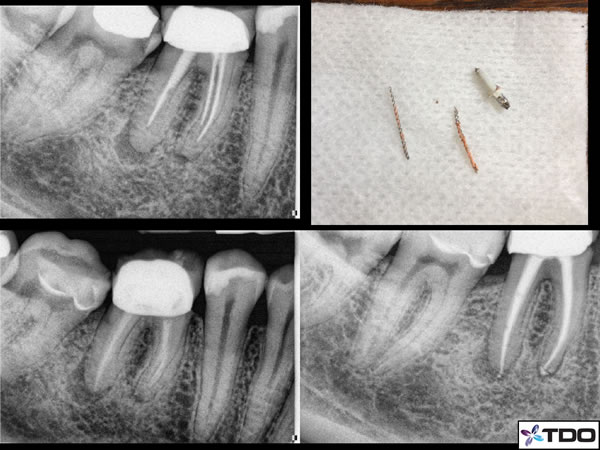

In figure 1, you will see an assortment of thermafil carriers of different sizes. Notice the obvious pinkish gutta percha that surrounds the “carrier” which runs through the middle of the gutta percha and extends out to the handle section. In this figure the carrier is a plastic core. I have also included a case I am currently treating with metal Thermafil carriers. Notice in the pre-operative x-ray the “file-like” appearance of the material in the mesial canals. This is easily mistaken for separated files. However you can see upon removal of the carriers there is gutta percha around the metal carrier. I also included an x-ray of calcium hydroxide in the canals following full instrumentation and the completed case.

Figure 1

One thing to remember is that rarely will a carrier dislodge at one attempt of this braiding technique. It always requires many attempts using new H-files and continuous repetition with standard hand filing and solvent use throughout. But patience typically always results in removal of the carrier material. The metal carriers in figure 1 were removed with this braiding technique.